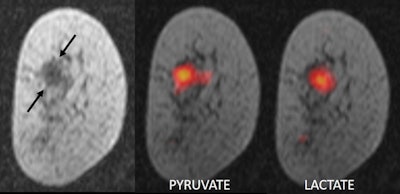

MR imaging of a breast tumor. Left panel: anatomic image of a breast cancer (arrows); middle panel: pyruvate in the tumor; right panel: lactate in the tumor. All images courtesy of Dr. Ramona Woitek, PhD.

Tumors make use of large amounts of sugar and take up more pyruvate than normal tissue, explained team member Dr. Ramona Woitek, PhD, from the University of Cambridge. Inside the tumor, pyruvate is converted into lactate as part of a natural metabolic process. Since magnetizing the carbon-13 pyruvate molecules increases the strength of the MRI signal by 10,000 times, the researchers can monitor this process and visualize it dynamically in MRI scans.

The scanner room showing a patient positioned in the MR scanner and the SPINlab hyperpolarizer in the room next door.The rate of pyruvate metabolism -- and the amount of lactate produced -- varies not only between different tumors but also between different regions of the same tumor. By monitoring this conversion in real-time, the researchers said they are able to determine the type of cancer being imaged. They can also determine how aggressive a tumor is, as faster-growing tumors convert pyruvate more rapidly than less-aggressive ones.